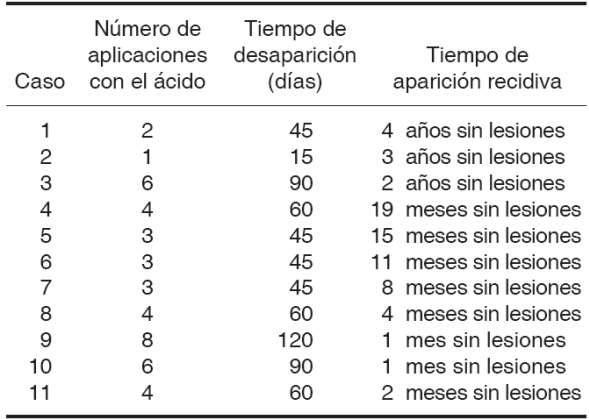

En mayor número de aplicaciones con el ácido fue tres y cuatro veces por caso representando 27% con un promedio 4.0 ± (DE:2.0), el promedio de desaparición de las lesiones fue de 61.3 días ± (DE:28.8) y en el 100% de los casos no se han presentado recidiva (Cuadro II).

Cuadro II Comportamiento de las lesiones con relación al número de aplicaciones, tiempo de desaparición y recidiva.

León et al, reportaron dos casos de pacientes afectados con HEF, en la mucosa labial superior e inferior y mucosa yugal, los cuales fueron tratados con ATA al 70% obteniendo buenos resultados en varias sesiones,18 Little et al, reportaron que la aplicación de ATA en la HEF es una alternativa terapéutica que muestra buenos resultados y recomiendan concentraciones entre 80 y 90%;25 coincidiendo con el presente trabajo donde se realizaron topicaciones con ATA al 80%, obteniendo buenos resultados con un promedio de desaparición de las lesiones de 61.3 días; sólo dos pacientes manifestaron sensación de ardor después de la aplicación del ácido en la primera sesión y no se ha presentado recidiva en el 100% de los casos.

Mata et al, aplicó ATA y crioterapia pacientes con HEF, observando resolución completa de las lesiones después de dos años de seguimiento;26 discrepando con dichos resultados ya que en el actual estudio, el promedio de desaparición de las lesiones fue de 61.3 días y sólo con topicaciones con ATA al 80%.